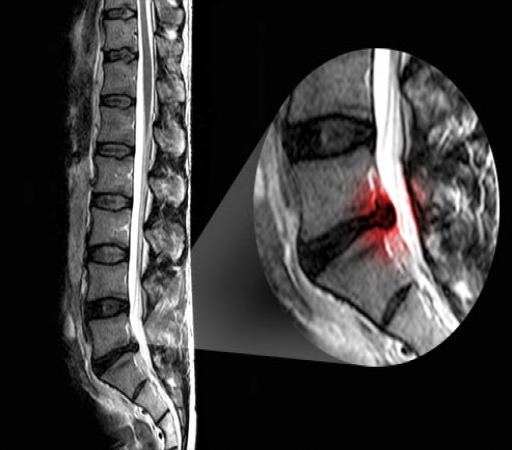

(فتق دیسک بین مهره ای) به انگلیسی (Intervertebral Disc Herniation) عارضه ای است که بعلت ضربه یا بلندکردن جسم سنگین و یا گاهی خود به خود در ستون فقرات اتفاق می افتد و طی آن آزاد شدن بخش مرکزی دیسک یا هسته دیسک (نوکلئوس پالپوزوس) از قسمت محیطی آن یعنی آنولوس فیبروزوس باعث فشار برروی ریشه های عصبی و ایجاد علائم بالینی می گردد. ...نظرات ارزشمند شما